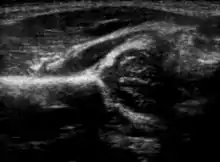

α and β angles used in hip ultrasound

Hip ultrasound

Imaging

Hip dysplasia can be diagnosed by ultrasound[42] and projectional radiography ("X-ray").[43] Ultrasound imaging is generally preferred at up to 4 months due to limited ossification of the femoral head up until then, and is the most accurate method for imaging of the hip during the first few months after birth. However, in most instances, ultrasound screening should not be performed before 3 to 4 weeks of age because of the normal physiologic laxity.[44][notes 1] When universal with targeted ultrasound screening was compared, the former results in an insignificant reduction in the late diagnosis of hip dysplasia, which is why universal ultrasonographic screening of newborn infants is not recommended by the American Academy of Pediatrics.[11]